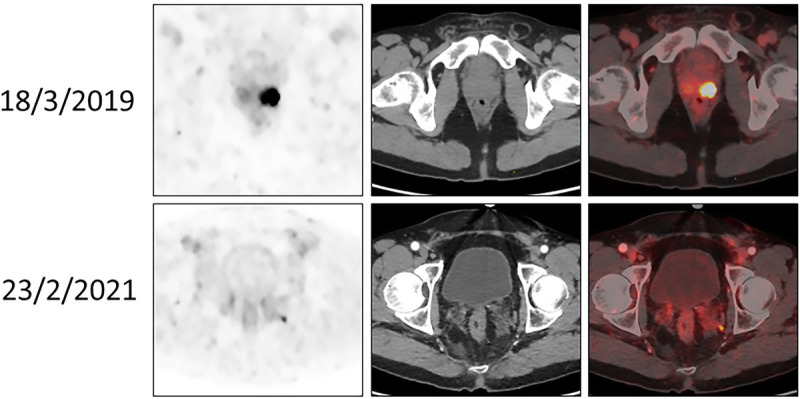

Materials and methods: Patients with intermediate/high risk PC showing no extraprostatic disease on PET/CT-PSMA underwent RP with PLND and were followed postoperatively for at least 6 months. Patients with detectable (>0.1 ng/mL) postoperative prostate-specific antigen levels underwent re-evaluation with PET/CT-PSMA.

Results: A total of 70 patients underwent RP for intermediate (34 patients) or high-risk disease (36 patients). According to the Partin, MSKCC, and Briganti 2012 nomograms, positive LNs were expected in 7, 13, and 12 patients, respectively. At PLND, 1 positive LN was found in a single patient (p < 0.05 compared with the expected number of patients from all nomograms). Postoperatively, 10 patients developed detectable prostate-specific antigen levels. One patient exhibited radioligand uptake that could indicate LN involvement. Considering these 2 patients as failures, the negative predictive value of PSMA-PET/CT for LN involvement was 97.1%.

Conclusions: Preoperative PSMA-PET/CT with no extraprostatic uptake before RP in patients with intermediate to high-grade PC is highly accurate for ruling out LN involvement, superior to the routinely used nomograms. Its use induced stage migration, rendering predictive nomograms irrelevant.